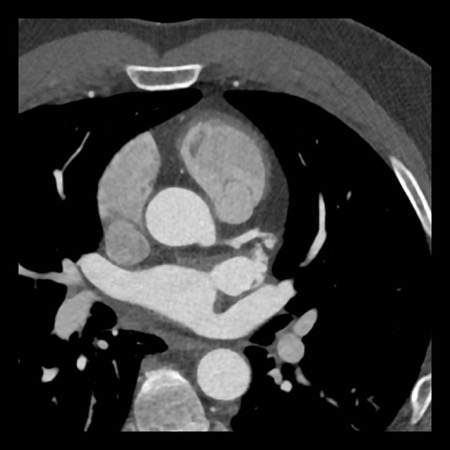

case 2 – CAD-RADS 5/P2/S

First, scroll through the CTA images.

How would you describe the findings on the coronary CTA?

The findings are:

- Stent in the mid

LAD with low-attenuation within the stent suggestive of minimal in-stent

restenosis (<25%). Non-calcified plaque distal to the stent

causing mild stenosis (25-49%). Notice bridging on a short segment in

the distal LAD. - Non-calcified

plaque in the LCX causing mild stenosis (25-49%). - Occlusion of the

proximal OM1 branch with distal filling. - Calcified and

non-calcified plaques in the proximal RCA causing mild (25-49%) stenosis. - Total plaque burden

is moderate based on SIS (four segments including proximal RCA, mid LAD, prox

LCX and OM1).

Due to the occlusion of OM1 branch and presence of the stent, this case

reads as CAD-RADS 5/P2/S, which means that this patient needs further

diagnostic workup.